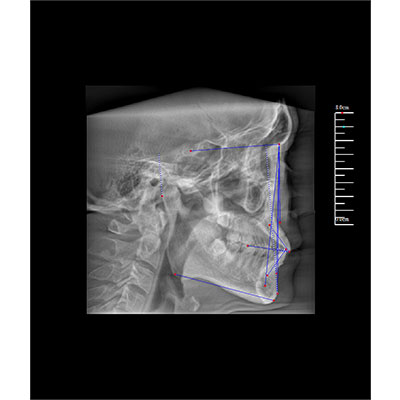

專有三維重建算法,可提供任意位置高清斷層影像。